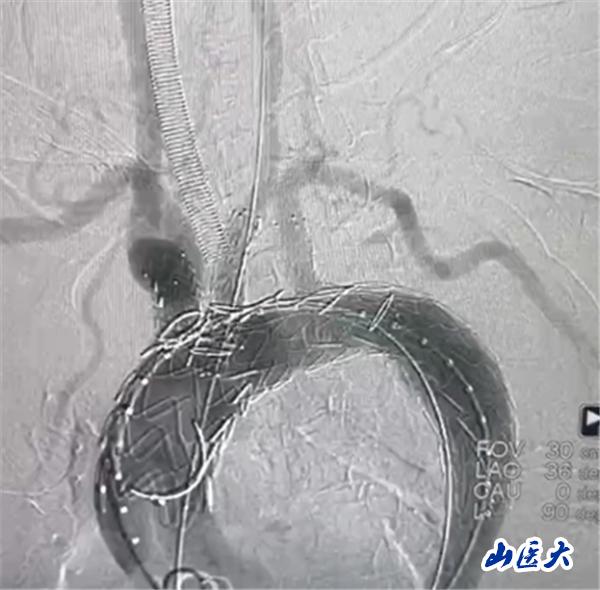

首例患者是一位55岁的女性,她患有高血压约2年时间,平时也会规律服用多种降压药,但血压控制始终不尽人意。2023年4月下午,她出现不明原因的头痛,在家拔罐缓解少许便未到医院就医,次日凌晨突感胸闷、胸背疼痛伴有呼吸困难等症状、家人急忙拨打了120,把患者送入医院急诊科进行救治,医生在急诊科行胸腹主动脉CTA时,显示主动脉弓部-降主动脉及腹主动脉壁间血肿,遂收治入医院血管外科,患者入院10天后复查血肿仍未有改善,依然伴有胸背部疼痛等不适,如不进一步处理,可能发展为夹层危及生命,患者及家属经过与医生团队了解沟通,决定进行创伤小、恢复快的介入手术治疗。张玮教授、符伟国教授、董红霖教授及其血管外科团队(闫盛、常文凯、田琴琴)共同商讨手术方案,最终确定使用Zipper™一体式主动脉弓覆膜支架系统,行胸主动脉覆膜支架腔内隔绝术+无名动脉、左颈总动脉、左锁骨下动脉分支重建术为患者进行治疗。董红霖教授及其血管外科团队根据患者术前头颅CT平扫提示双侧侧脑室旁缺血灶,血压控制不稳定,属夹层壁间血肿非典型夹层等风险点,制定了完整的手术方案,术中经股动脉置入Zipper支架主体,经预留导丝超选无名动脉,并确保主体支架对位准确,顺利置入左颈总动脉、左锁骨下动脉支架,重建弓上三分支。手术过程非常顺利。术后观察主动脉及分支覆膜支架定位准确;无内漏;分支支架通畅,动脉供血正常。

术后效果